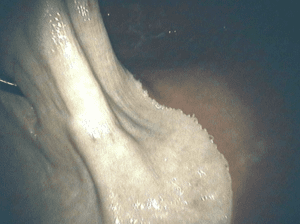

Normal Greater Curvature

Normal Lesser Curvature